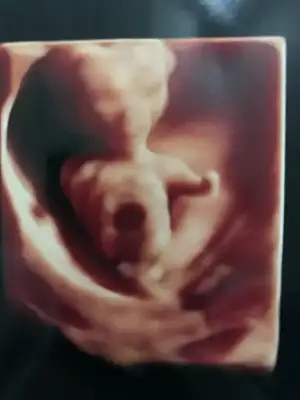

Ikra meyra Ikra meyra banada kesenden tahminde bulunabilir misin. Vajinal bakıldı ilki 6. Hafta ikincisi 7. Hafta.Biliyorum çok erken ama tecrübelerine dayanarak tahminde bulunursan sevinirim.🎈

Eklentiler

• 71AD2650-BD92-48E6-BEF6-626DE88E9F74.webp

71AD2650-BD92-48E6-BEF6-626DE88E9F74.webp

41,5 KB · Görüntüleme: 55

• E0700021-9419-462F-BEF7-9E98306A694F.webp

E0700021-9419-462F-BEF7-9E98306A694F.webp

38 KB · Görüntüleme: 57